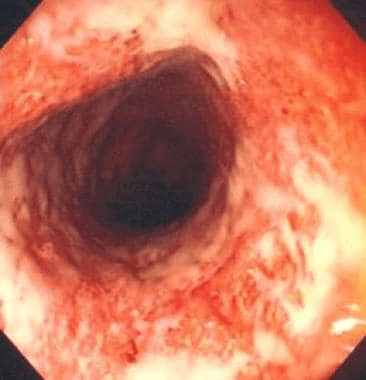

A 27-year-old man presents with 3 months of bloody diarrhea, urgency, and tenesmus. He reports 6–8 bowel movements per day and unintentional weight loss. He has no recent travel or antibiotic exposure.

Laboratory studies show: Mild anemia and Elevated CRP

Colonoscopy demonstrates these findings:

What is the diagnosis?

Ulcerative colitis